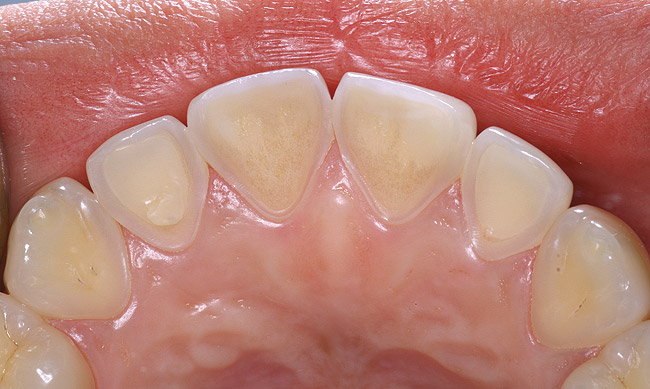

Figure 4  A patient with history of bulimia has dental erosion on the lingual surfaces of her maxillary incisors.

Figure 4

If a patient has risk factors that can contribute to dental erosion, an examination will reveal clinical signs and symptoms of dental erosion. It is unlikely that dental erosion will be seen without other contributing factors. Tooth wear and abrasion typically occur in combination with dental erosion. In the clinical evaluation of tooth surfaces for the diagnosis of erosion, what is typically seen are smooth, shiny surfaces of the teeth where the usual anatomic form of the tooth should be. In patients ingesting very acidic diets, the facial surfaces of anterior teeth are very smooth, and if the beverages being ingested have high sugar content, these teeth may have caries at their facial gingival margins (Figure 1). The occlusal surfaces of posterior teeth in the more advanced stages of erosion due to regurgitation may have extensive exposed dentinal areas with loss of anatomic form (Figure 2). In some cases, the chemical erosion combined with toothbrush–toothpaste abrasion can remove all the enamel, leaving only the dentin exposed (Figure 3). These teeth may exhibit sensitivity. Posterior teeth with restorations may demonstrate fillings that are higher than the surrounding occlusal surfaces of the enamel. Anterior teeth may demonstrate more incisal translucency due to tooth loss at the incisal edge. In patients with the eating disorder bulimia nervosa, who vomit, the hydrochloric acid causes extensive damage to the lingual surfaces of the anterior teeth, where the enamel is lost, leaving exposed dentin (Figure 4).